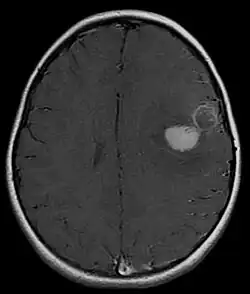

![]() RMN cerebral con contraste de PNETs en niña de 5 años afectando sobre área motora del habla (Broca) con sangrado intraparenquimatoso. | ||

El Tumor neuroectodérmico primitivo supratentorial (PNETs) es un tumor maligno de estirpe embrionario ( células neuroepiteliales indiferenciadas o pobremente indiferenciadas). Todos corresponden a un grado IV de la OMS (velocidad de crecimiento tumoral acelerado) afectando principalmente a niños. El 65% se diagnostican en niños menores de 5 años de edad. Corresponde al 2,5 - 6 % de todos los tumores cerebrales en niños. Aunque raro, pueden presentarse también en adultos. No existe predilección de géneros afectando por igual tanto al sexo masculino como al femenino. Histológicamente es indistinguible del Meduloblastoma (otro tumor embrionario maligno) aunque se comporta de forma más agresiva que este y con menor tasa de superveniencia. Suele observarse comúnmente en el cerebro y por ser altamente propenso a su diseminación, podemos encontrarlo en la médula espinal y región supraselar del cerebro (área alrededor del quiasma óptico). El tratamiento de elección es la neurocirugía con adyuvancia de radioterapia y quimioterapia. El diagnóstico definitivo lo confirma la anatomía patológica después de la cirugía.

- Resonancia magnética cerebral (RMN): la parte sólida es isointensa (misma intensidad) comparada con la corteza en el T2WI. Captación moderada de contraste. Se puede observar zonas hemorrágicas y quístcas. siembras en espacio subaracnoideo se suelen observar en el 36% de los pacientes. Reducción de la difusión en DWI. En la Espectroscopia es característico la disminución de NAA y aumento de colina y de lactato/lípido.